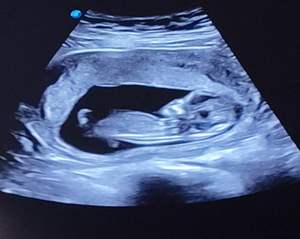

فردا میخام جشن تعیین جنسیت بگیرم بیاین حدس بزنین

از علائمم بگم براتون

اصلا هیچ دردی نداشتم تا همین الان که 17 هفته ام

حالت تهوع و استفراغ داشتم اوایل ولی الان فقط تهوع دارم

شکمم اصلا بزرگ نشده و هیچی حس نمیکنم

وزنم کم شده و چهرمم هیچ فرقی نکرده اصلا معلوم نیست که باردارم

اوایل بارداری هم درد سمت راست داشتم تخمدان راستم درد میکرد البته فقط یه تخمدان دارم سمت راست